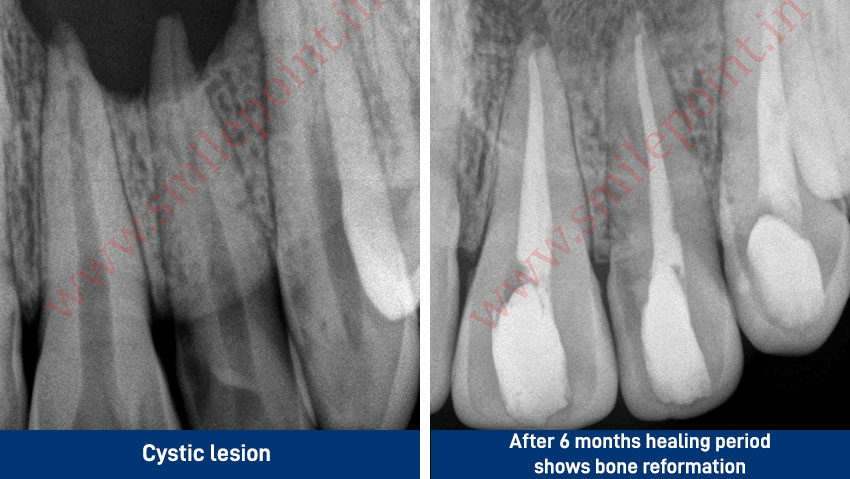

Computer Assisted Root Canal Treatment